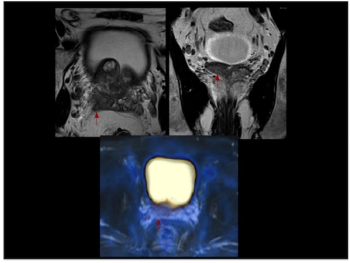

In a cohort of 85 patients with biomechanical recurrence of prostate cancer and PSA values less than 2 ng/mL, positive findings on PET imaging with PSMA-18F DCFPyL led to treatment changes in the majority of patients who had negative findings on conventional imaging, according to new research presented at the SNMMI conference.